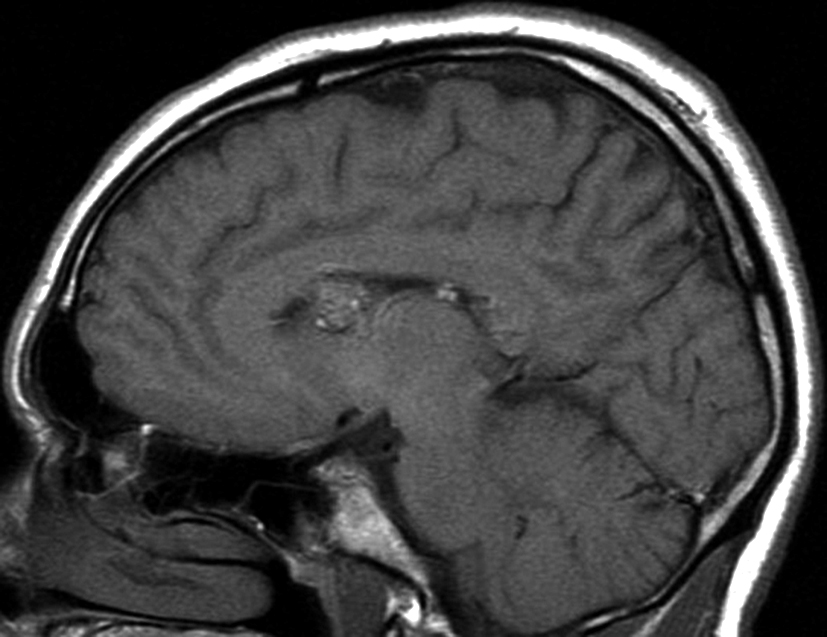

Figura 3

a y b) Imágenes sagitales T1, A. se observa la lesión a nivel del asta frontal de ventrículo lateral derecho y B. se evidencia la extensión al cuerpo calloso.